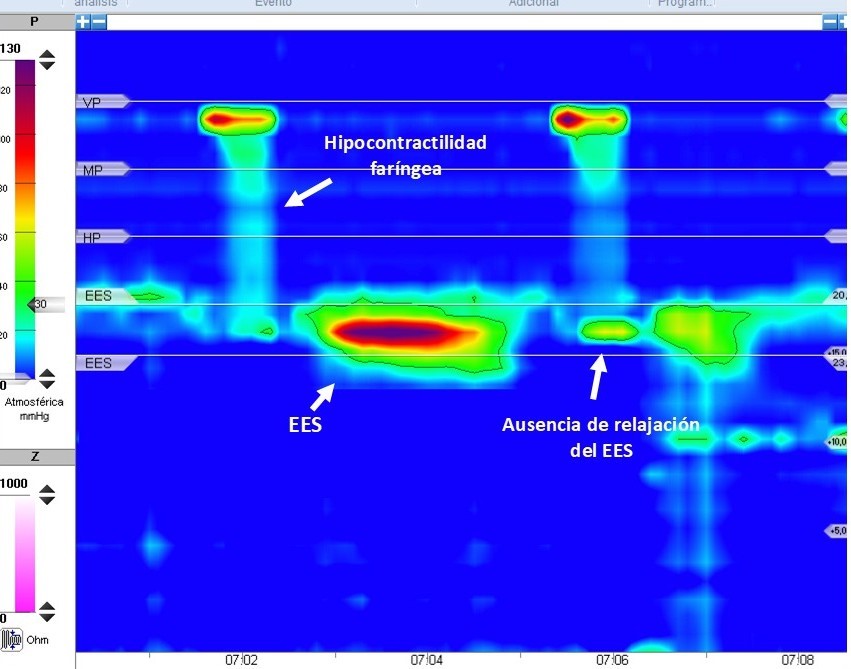

Fue valorada por ORL, que descartó lesiones estructurales relevantes, aunque observó retención de saliva en senos piriformes. La endoscopia digestiva alta reveló estenosis esofágica a nivel cricofaríngeo, con dificultad para el paso del endoscopio y desgarro mucoso incidental, con biopsias esofágicas sin alteraciones. Se realizó un TAC que descartaba compresión extrínseca. El estudio esófago-gastroduodenal (EGD) con videofluoroscopia mostró una gran dilatación faríngea con restos alimentarios retenidos en senos piriformes secundaria a estenosis de contornos regulares en la transición faringo-esofágica de 2,6 cm (Figura 1).

Figura 1. - Videofluoroscopia evidenciando una gran dilatación faríngea con restos alimentarios retenidos en senos piriformes y estenosis de contornos regulares en la transición faringo-esofágica de 2,6 cm sugerente de impronta del músculo cricofaríngeo.